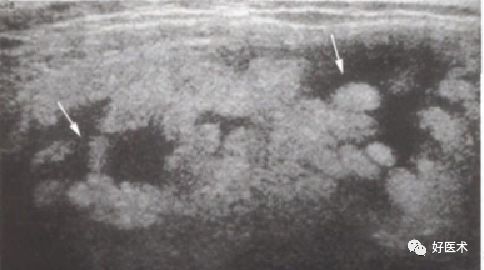

超 声

(1)关节积液:尤其是髌上囊及左右侧囊

(2)关节内病变:滑膜弥慢性增生、肥厚,可见大小不等形状不规则的实性团块状回声,呈低、中等或高回声,分布不均匀;半月板及交叉韧带边缘模糊不清,股骨或胫骨边界不光滑或局部呈锯齿状改变

(3)关节外病变:周围软组织内有结节状或分叶状不均质回声区

髌上囊多个等回声结节,可见绒毛状突起

髌上囊内液性暗区,滑膜不同程度增厚,呈结节状